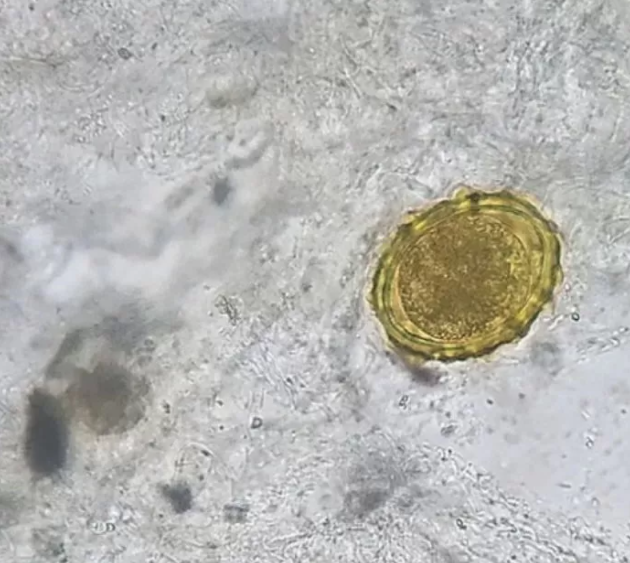

회충증은 기생충과 같은 회충이 사람의 장이나 위에 기생하여 일으키는 감염병의 하나로 회충의 충란이 포함된 음식을 섭취하면서 감염하게 됩니다. 감염 환자가 충란이 섞인 변을 배설할 때 이게 흙에 섞이게 되면 또 다른 사람의 체내로 들어가면서 병이 전파되게 됩니다.